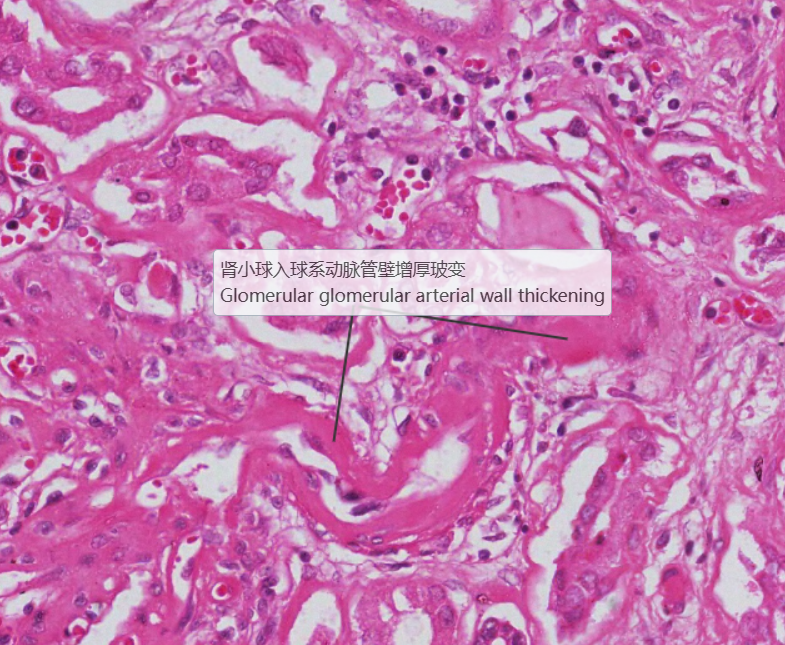

糖尿病肾病:1.大部分肾小球系膜区大量基质增多,较多形成结节状扩大,少数细胞靠结节边缘排列, 形成典型的K-W结节。部分节段有系膜细胞轻度增生, 基膜增厚。2.少数小球伴有球囊壁纤维化。 少部分肾小球硬化(玻璃样小体)。3.肾小管较多灶性萎缩,部分肾小管扩张,管腔内有蛋白管型。4.间质广泛纤维化,伴大量炎症细胞浸润(淋巴细胞、浆细胞)。许多肾小球入球细动脉壁增厚玻变, 间质肌性小动脉内膜增厚纤维化。

5.入球微动脉管壁增厚